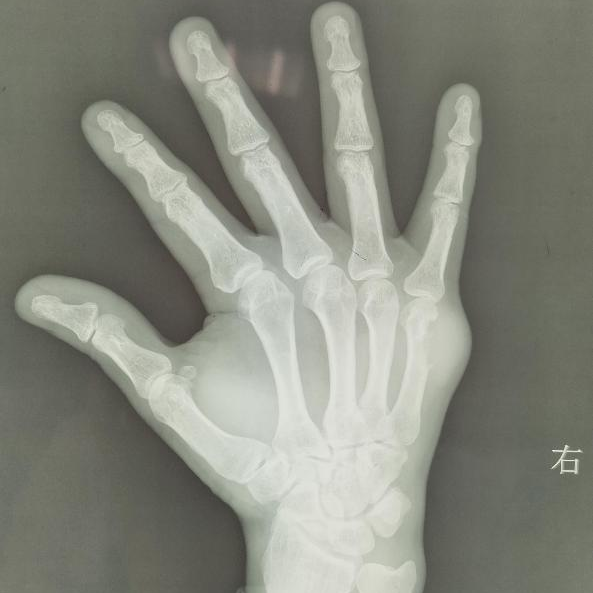

近日,我院道门口院部肾病(风湿免疫)科与超声科协作,成功救治一名严重痛风患者。患者患痛风多年,长期院外自购药物,未正规诊治。到科室就诊时关节疼痛剧烈,双膝关节肿胀压痛明显,多处关节畸形,痛风石形成(如图一)。血尿酸及炎性指标明显升高,X片示骨质破坏(图四)。

图一:患者右手关节

图四:患者右手X 片